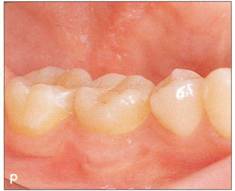

Fi 545e45f g 5-10 Stabilization of the donor tooth. The donor tooth has been splinted to the adjacent tooth with twisted wire and selfcured composite resin after etching and bonding. Fi 545e45f g 5-1 p After transplantation. |

Fi 545e45f g 5-15 Three weeks after transplantation. Root canal therapy was started 2 weeks after transplantation. After temporary obturation with calcium hydroxide, the root canal was obturated with gutta percha in 5 weeks. Fi 545e45f g 5-1t Two and one half months after transplantation. |

Fi 545e45f g 5-1 u Definitive occlusal restoration of the donor tooth with composite resin. Fi 545e45f g 5-1v One year 3 months after transplantation. Normal periodontal ligament space and lamina dura are observed. |